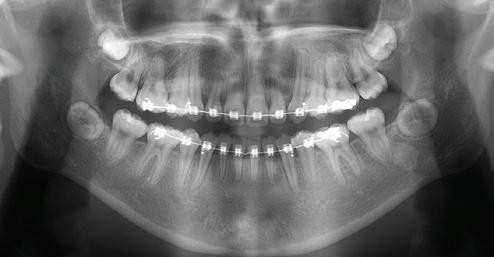

The panoramic radiograph (Figure 3) reveals transposition of the roots of the maxillary right first premolar (#5) and the adjacent unerupted canine (#6). As it turns out, this finding prompted the referral from the general dentist. Tooth #13 is mechanically obstructed and appears to be displaced transversely. The ‘shovel-shaped’ maxillary incisors with their prominent proximal lingual ridges are also apparent on the panoramic radiograph.

Figure 3: Initial panoramic radiograph